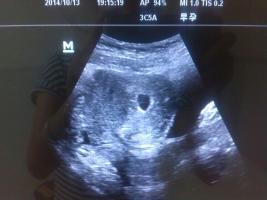

谁能帮忙看B超图片,以下是孕40天与孕13周照的B超图,现在是二胎压力大啊,请帮忙看看吧